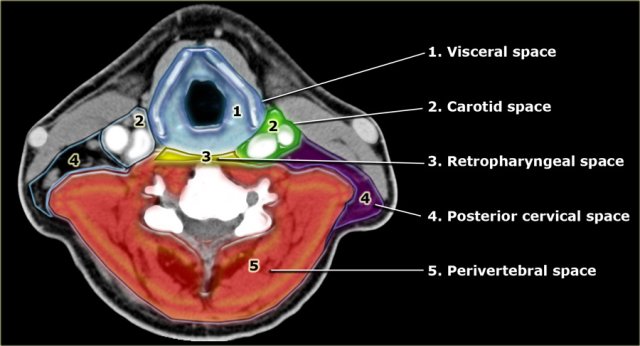

The infrahyoid neck is divided into 5 major anatomical compartments or spaces by the various layers of the cervical fascia (2).

These spaces are well recognized in the axial plane and therefore suited for analysis on axial CT or MR.

- Visceral space

Central compartment containing several viscera like the larynx, thyroid, hypopharynx and cervical esophagus. - Carotid space

Paired space just lateral to the visceral compartment which contains the internal carotid artery, internal jugular vein and several neural structures. - Retropharyngeal space

A small virtual space containing only fat continuous with the suprahyoid space and the middle mediastinum. - Posterior Cervical Space

Paired space posterolateral to the carotid space.

It contains fat, lymph nodes and neural elements. - Perivertebral space

This large space completely encircles the vertebral body including the pre- and paravertebral muscles.